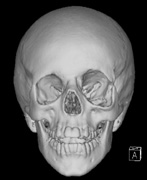

- Congenital absence of the greater wing of the Sphenoid bone

Growth of a plexiform neuroma may be directed posteriorly, infiltrating orbital tissues and involving the bony walls. Congenital plexiform neuromas of the orbit are often associated with absence of the sphenoid wing (Fig. 5). Intracranial pulsation can be transmitted to the orbit causing pulsatile proptosis or enophthalmos.57–59 Plexiform neuromas of the lid and orbit are difficult to treat; complete excision is difficult and potentially disfiguring. The tumors are vascular and may bleed copiously at surgery. They are not radiosensitive and there is also risk of inducing malignant transformation. Trials with antiangiogenic chemotherapeutic agents (thalidomide, interferon alpha) and mitotic-signaling pathway blockers (inhibition of Ras by Farnesyl protein tranferase inhibitor) are in progress.60,61

- A “distinctive” bone lesion: sphenoid bone dysplasia or thinning of long bone cortex (with or without pseudoarthrosis)